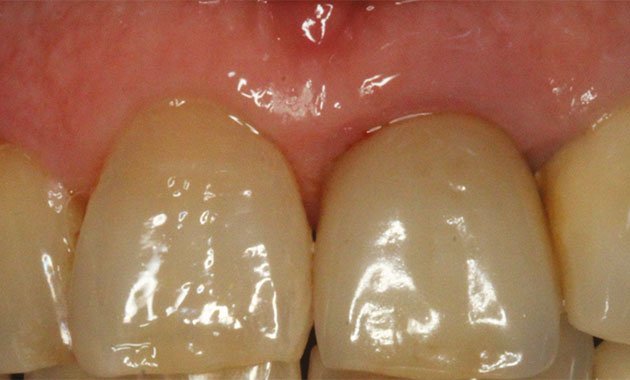

L'extraction-implantation immédiate

Un challenge thérapeutique boosté par l'audace clinique et l'évolution technologique.

L'extraction-implantation immédiate (EII) fait partie des premiers protocoles implantaires qui ont historiquement remis en cause les principes édictés par l'école suédoise pour garantir l'ostéointégration de nos implants [1]. L'axiome concerné s'énonçait ainsi : « implanter dans un os sain et parfaitement cicatrisé ». Alors que nous étions une poignée de praticiens à mettre en œuvre et promouvoir cette technique dès la fin des années 80, nous l'avons très vite agrémentée des nouvelles procédures de régénération osseuse guidée [2, 3]... Autant de bravades qui nous furent largement reprochées à l'époque par la doxa universitaire française, mais qui aujourd'hui sont admises comme des évidences.